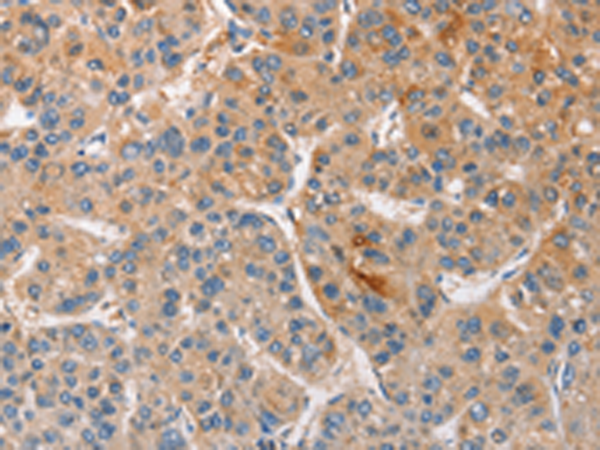

分类: 科研抗体货号: P07154别名: Car3; CAIII应用: WB,IHC反应种属: Human, Mouse, Rat